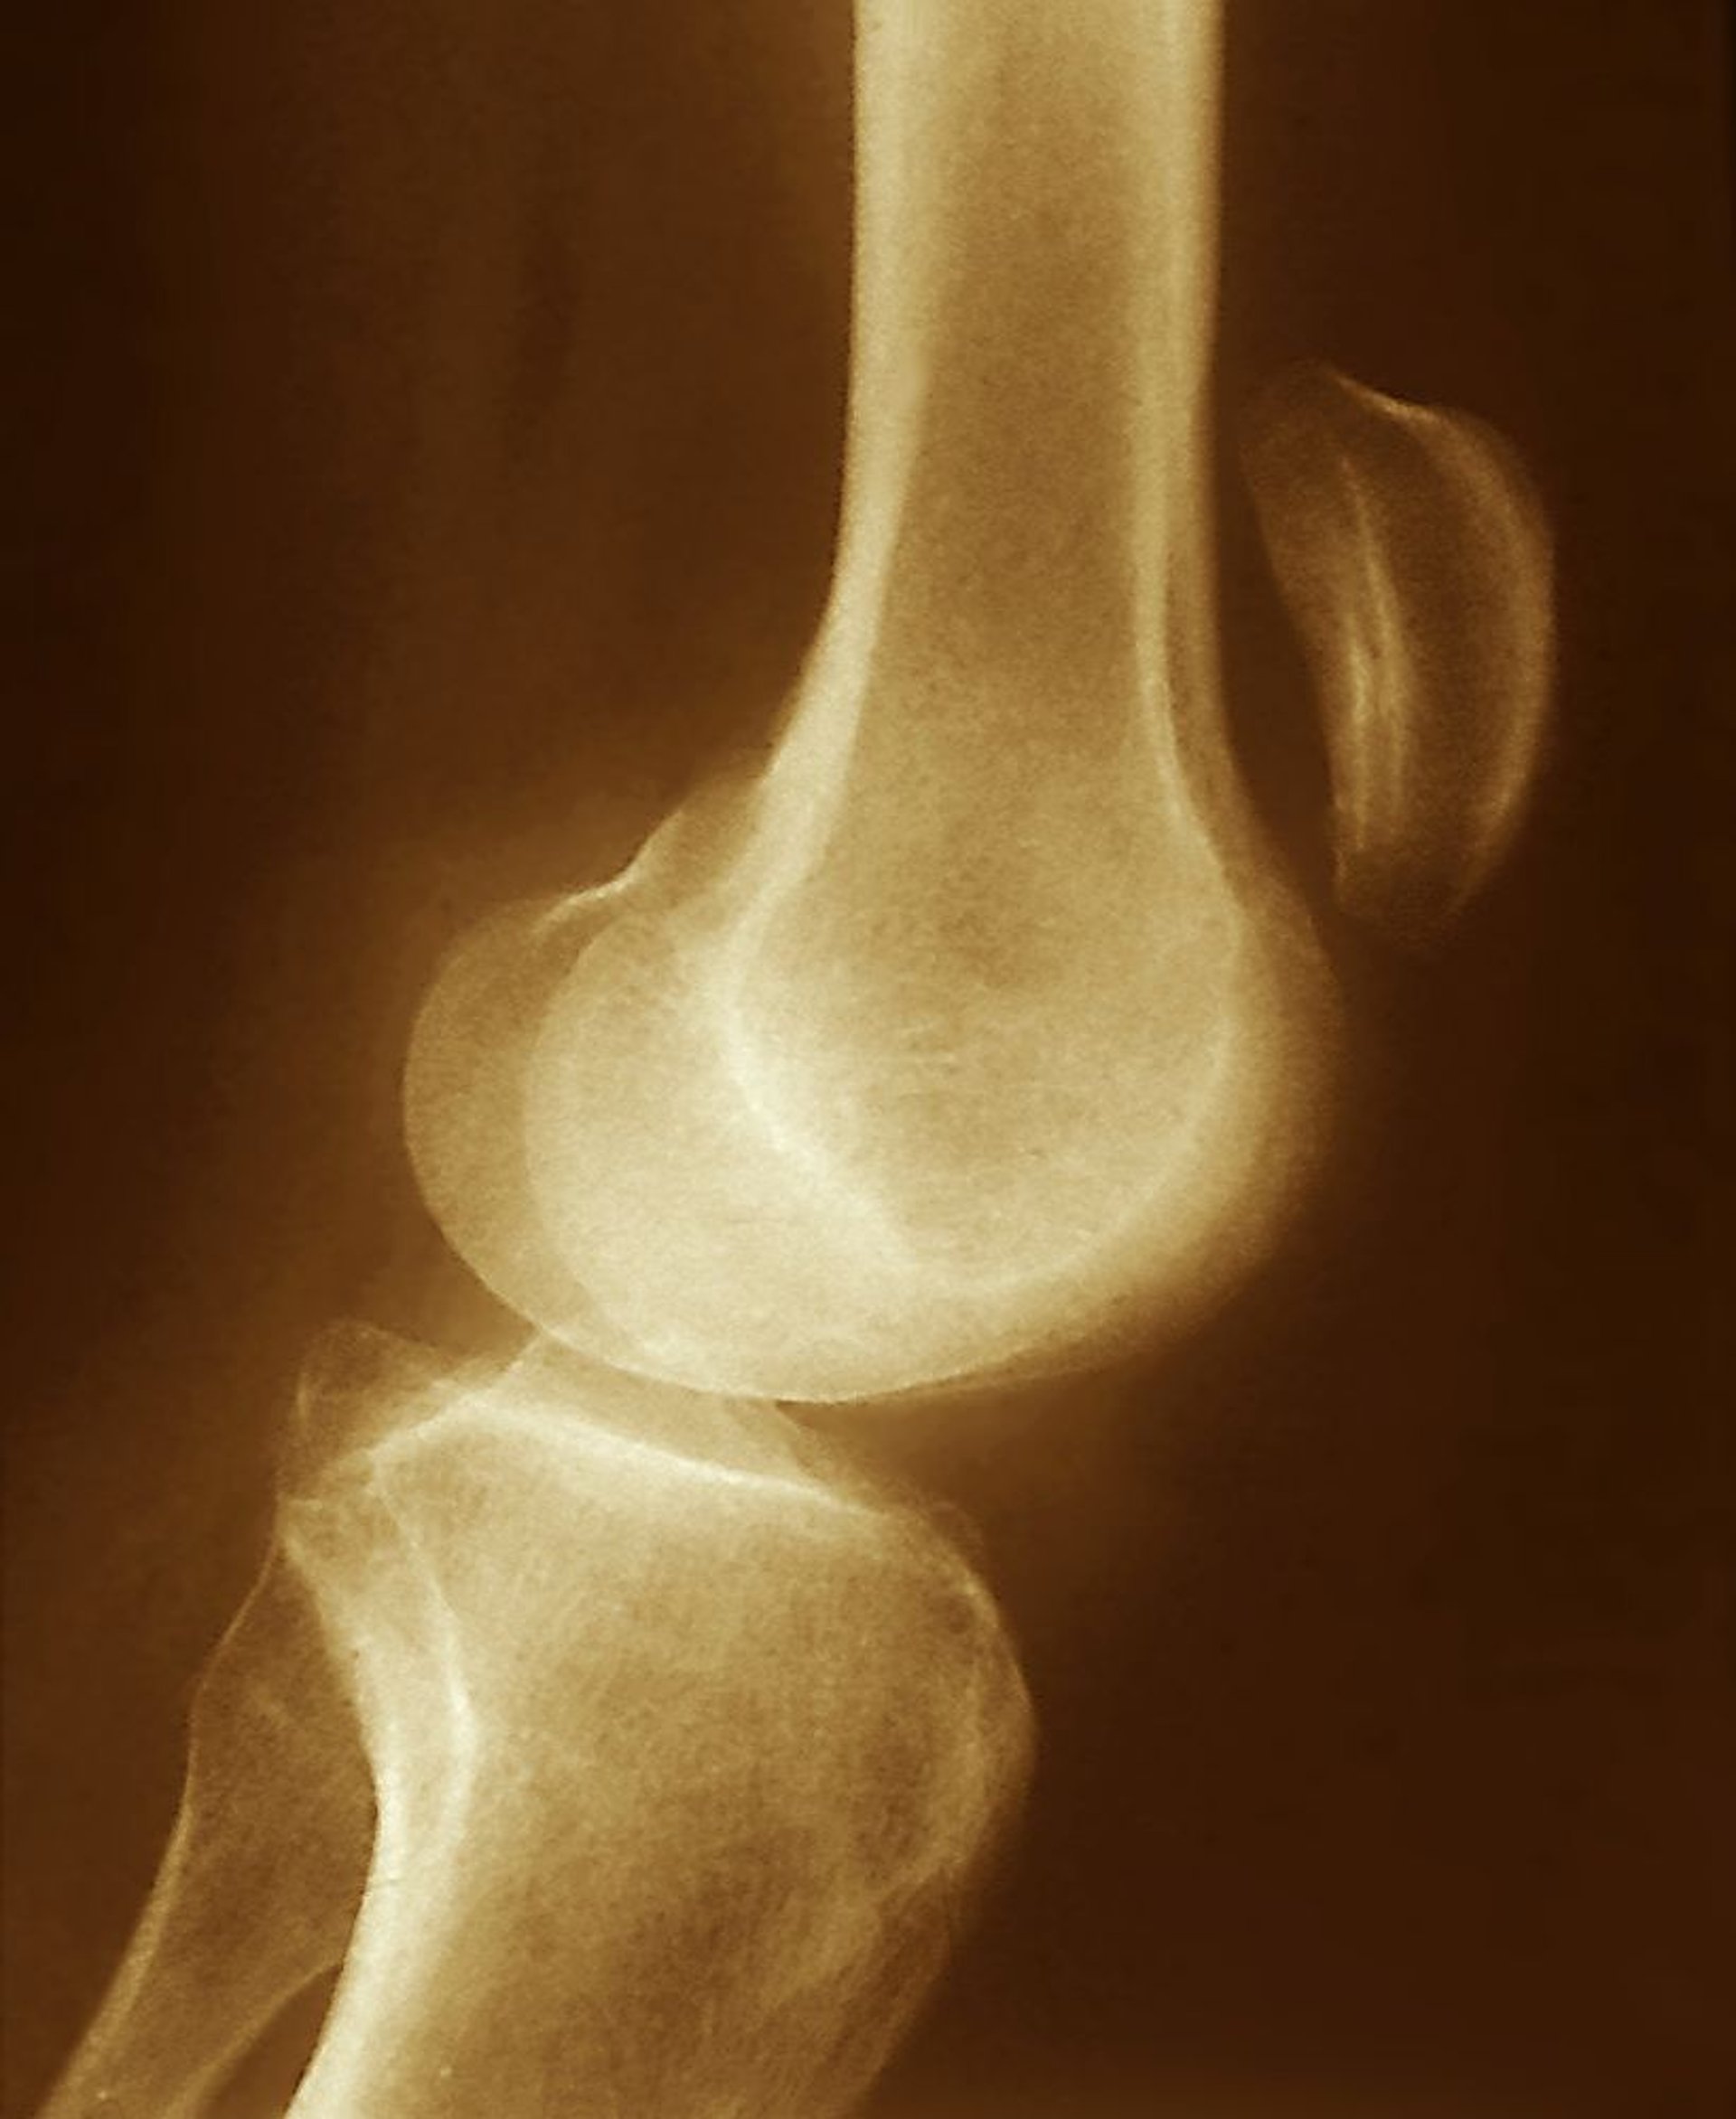

Patellarsehnenruptur

Die auf diesem Röntgenbild zu sehende Verschiebung der Patella nach oben (weit oberhalb des Kniegelenks) deutet auf einen Riss der Patellasehne mit unkontrollierter Kontraktion des M. quadriceps hin.

ZEPHYR/SCIENCE PHOTO LIBRARY